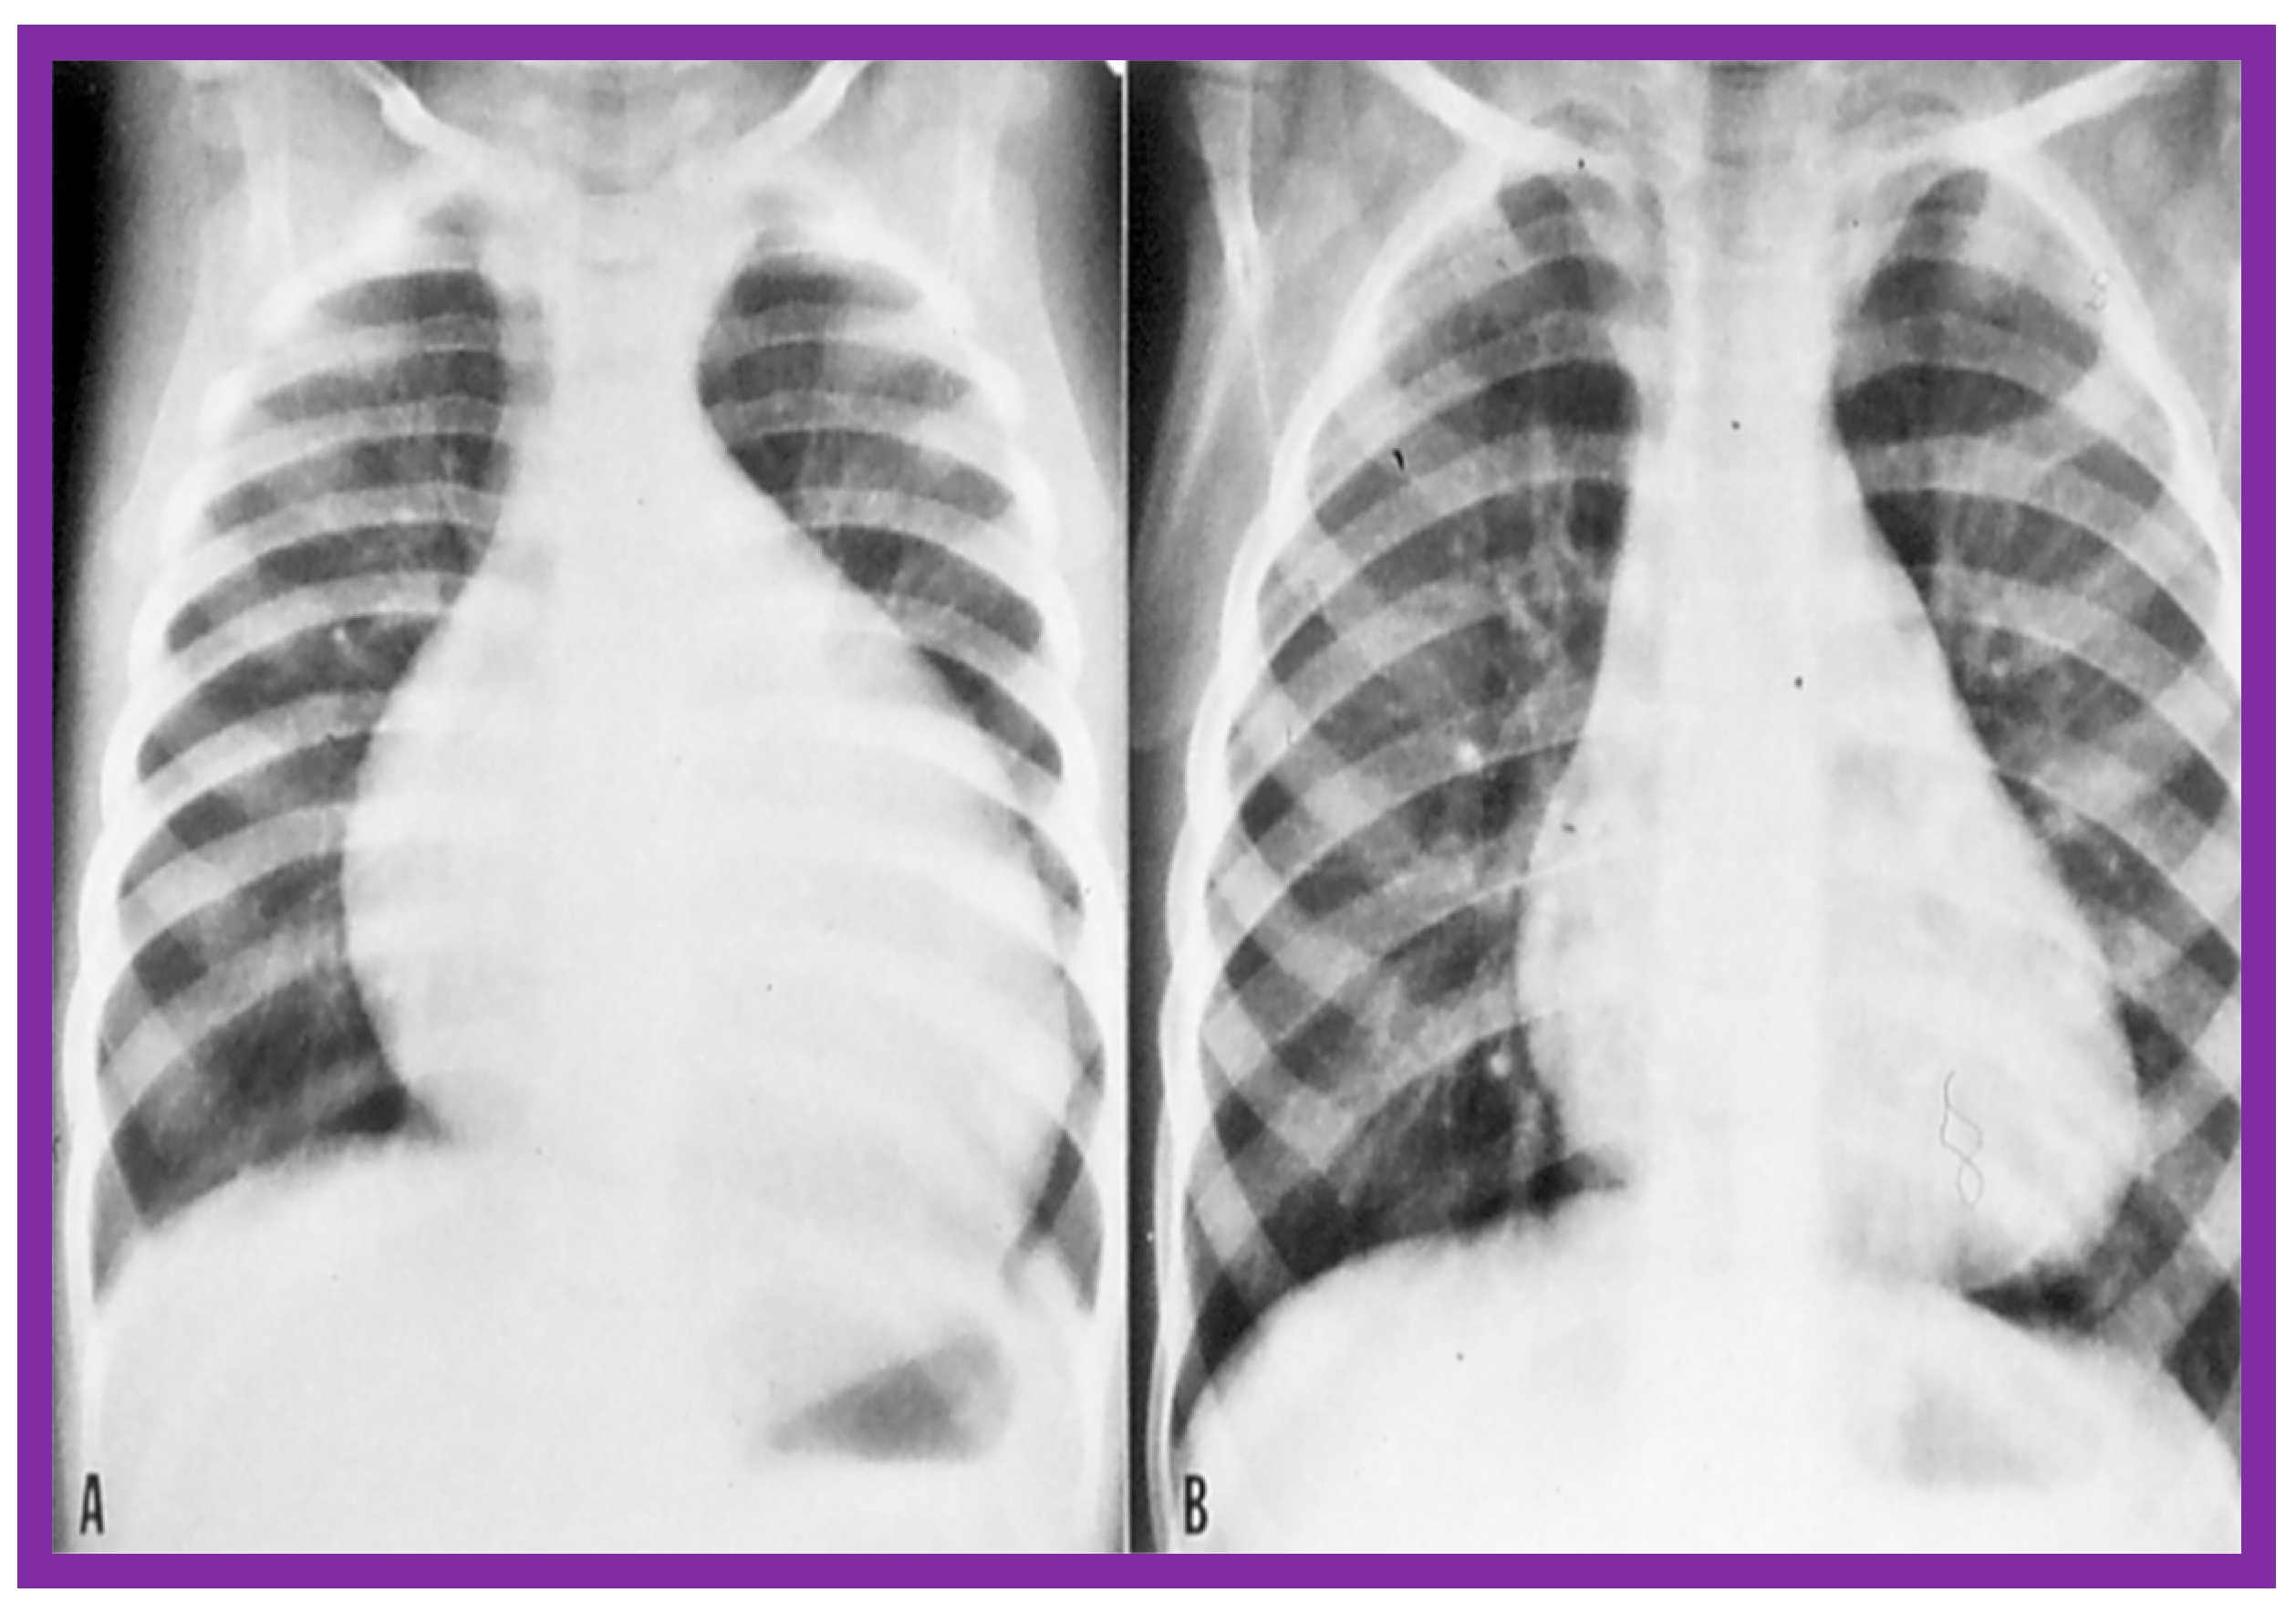

4.3. Aortic Coarctation–Native

Revisit BA in the Neonate and Young Infant